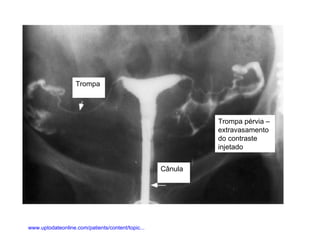

Sistema Reprodutor Ógãos que produzem, transportam e armazenam células germinativas Testículos  e ovários produzem células germinativas maduras.  Órgãos de transporte e armazenamento Homem: Ducto deferente,  próstata e  pênis Mulher: útero,  trompas uterinas e  vagina

Trompa Trompa pérvia – extravasamento do contraste injetado Cânula www.uptodateonline.com/patients/content/topic...

Sistema Reprodutor Ógãosque produzem, transportam e armazenam células germinativas Testículos e ovários produzem células germinativas maduras. Órgãos de transporte e armazenamento Homem: Ducto deferente, próstata e pênis Mulher: útero, trompas uterinas e vagina

Trompa Trompa pérvia– extravasamento do contraste injetado Cânula www.uptodateonline.com/patients/content/topic...